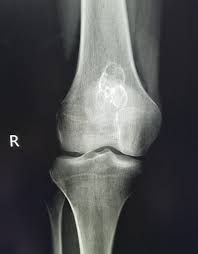

With an enchondroma, you may have no symptoms at all. The following are the most common symptoms of an enchondroma. However, each person may experience symptoms differently. Symptoms may include: Hand pain, if the tumor is very large or if the affected bone has weakened and caused a hand fracture Enlargement of the affected finger Slow bone growth in the affected area The symptoms of enchondroma may look like other medical problems. Always talk with your healthcare provider for a diagnosis